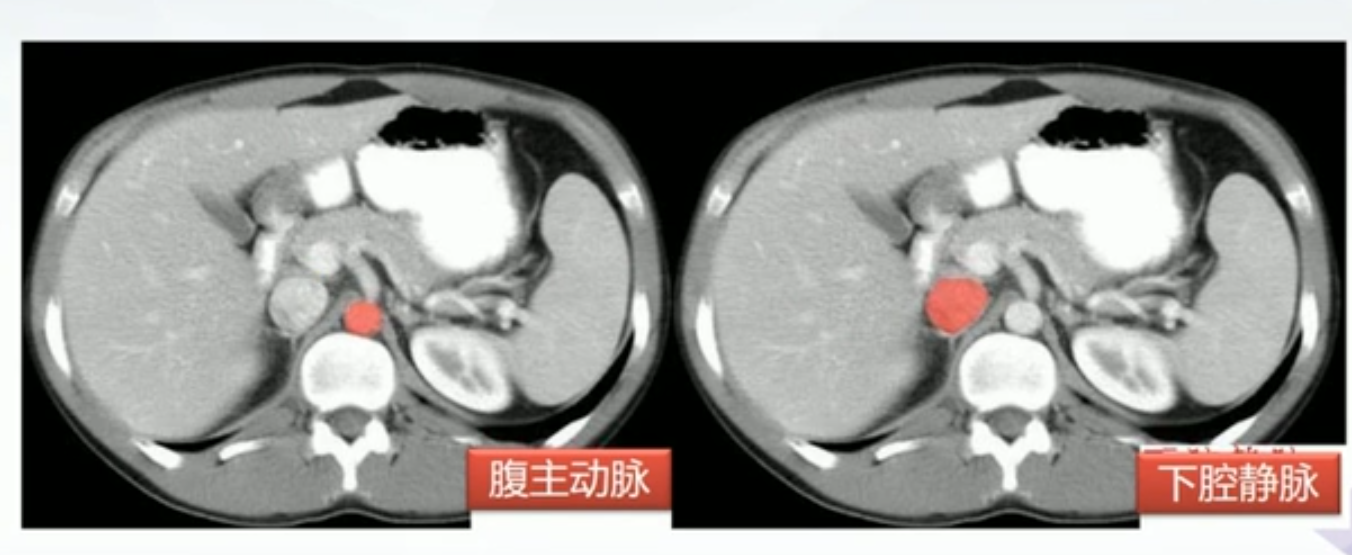

肝CT

- 40~60HU,高于胰,脾

- 肝内管道系统(胆管,肝动脉静脉和门静脉)低于实质,周围小分支多不显示。大血管呈低密度树状影

正常肝重要结构